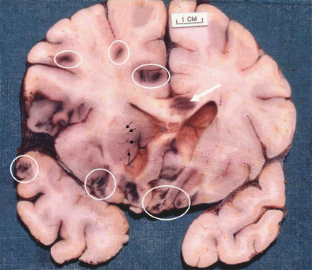

Fig. 3